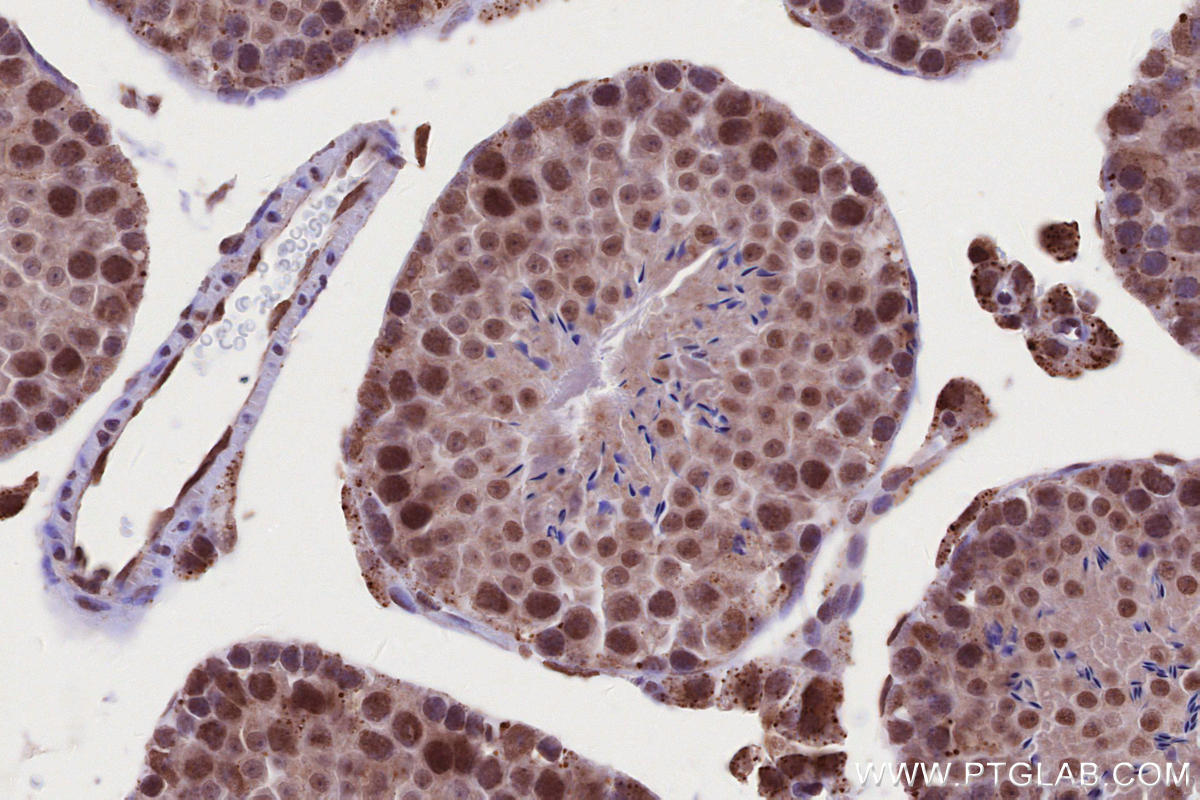

Validation Data Gallery